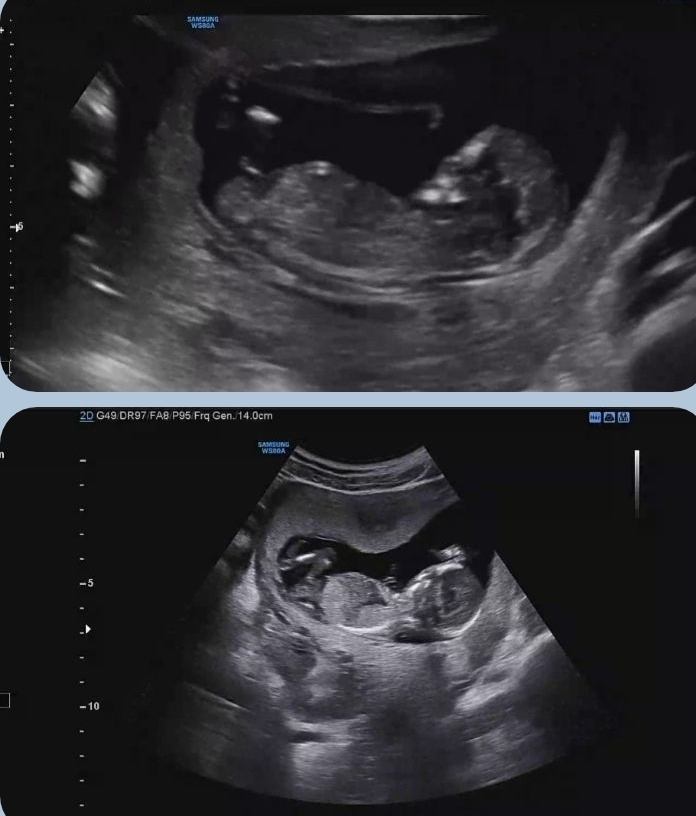

13주4일차에요:-)

쉴 틈없이 건강하게 잘 논다고 하더라구요. 보이질 않으니까 더 궁금하고 걱정되고ㅠㅠ 첫째라 그런지 더 그런가봐요. 다 그런거죵? 성별도 너무 궁금한데 첫째는 딸랑구 원하긴 하는데 선생님이 살짝 아빠 닮은것 같다는데 성별 반전이 있을까요^^ 어때 보이시나용???